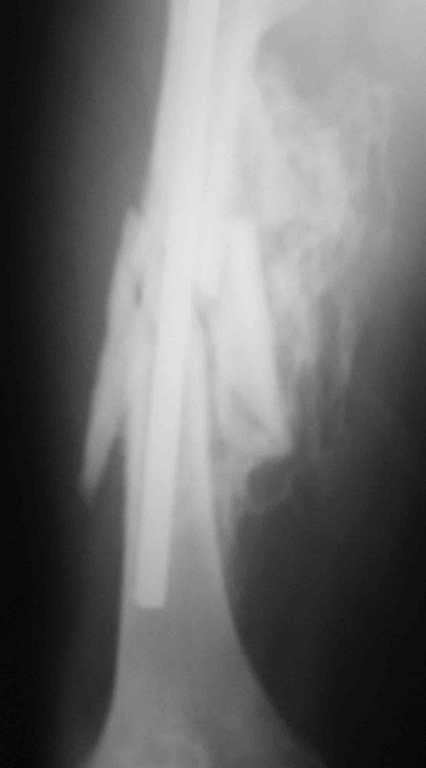

Re: 32- летний пациент с переломами обоих бедер по

Иллюстрации к сообщению